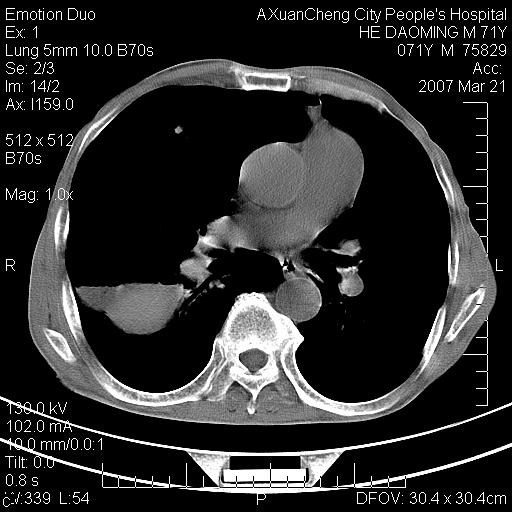

标题: CT7269:[原创] 咳嗽,咳痰,大家讨论右肺病变的部位 [打印本页]

标题: CT7269:[原创] 咳嗽,咳痰,大家讨论右肺病变的部位

1.慢支肺气肿 肺心病 肺大泡;2.叶间裂积液,前胸膜粘连

右侧相当于叶间软组织样密度ct值约50hu,请大家讨论是什么性者病变

考虑:慢性支气管炎合并全小型肺气肿、肺大泡、间质纤维化、感染,右斜裂积液。

考虑慢支,肺气肿,肺大泡,间质纤维化;右侧斜裂液气胸考虑(可能因为肺大泡破裂破入斜裂所致).

考虑病变以右上中肺多发肺大泡为主并感染。请结合临床考虑慢支肺气肿,肺心病。

1双肺慢性支气管炎并全小叶型肺气肿肺大泡2间质性纤维化3右侧斜裂积液

考虑:慢性支气管炎合并右侧全小型肺气肿、肺大泡并感染、双肺间质纤维化,右斜裂积液。

如果患者变化一下体位扫描可分辨液平与斜裂的关系。